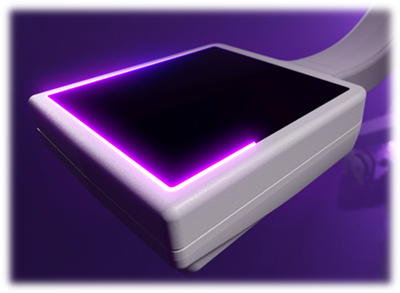

15cm x 15cm CMOSフラットディテクタ搭載

四肢専用ならではの低線量条件において高いX線利用効率を誇るCMOSフラットディテクタを採用。新たに15cm x 15cmサイズのディテクタを搭載することで撮影視野が旧モデルと比較して+33%拡大,四肢整形手術における画像診断ワークフローを最大化します。

・15cm x 15cm CMOSフラットディテクタ

・CMOS検出器 1.5K×1.5Kピクセル